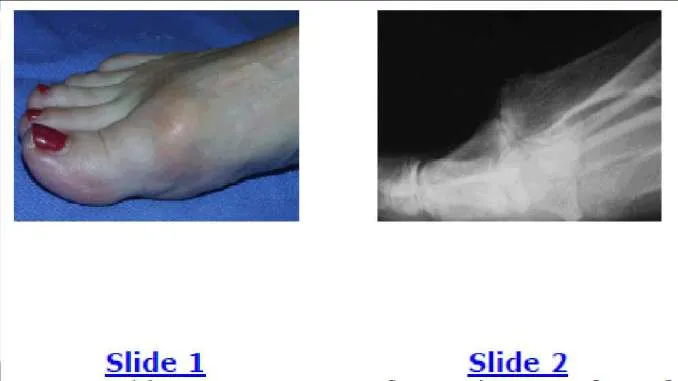

A 53-year-old man presents with a swollen foot. He does not recall any injury to the foot, and he has minimal pain. He does not have any pertinent medical history. The clinical and radiographic appearance of the foot is presented (Slide 1 and Slide 2). Based upon the information, the recommended treatment of this injury is:

Correct Answer: Open reduction and internal fixation (ORIF)

Patients with neuropathy may present for the first time with a neuropathic dislocation (C harcot neuroarthropathy) even before the cause of the neuropathy is diagnosed. The recommended treatment of an acute neuropathic midfoot dislocation is open reduction and primary arthrodesis. Although ORIF without arthrodesis may be considered, recurrent deformity frequently occurs.